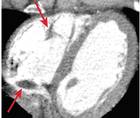

Interventional Neuromuscular Ultrasound

John Norbury, MD; Michael S. Cartwright, MD, MSJohn Norbury, MD; Michael S. Cartwright, MD, MS